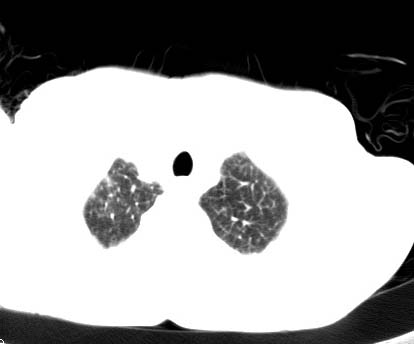

标题: CT14027:男性病人 71岁 咳嗽咳痰数周. [打印本页]

标题: CT14027:男性病人 71岁 咳嗽咳痰数周.

男性病人 71岁 咳嗽咳痰数周.诊断结核应该有保障吧!

右上肺结核,请结合痰检除外活动期;右上叶支气管官腔狭窄建议支气管镜或抗僗后随诊除外堵塞性改变。

结核是要考虑,但肺癌也不能排除.

高度怀疑肺癌,强烈要求纤支镜检查。

支持双上肺继发性肺结核。